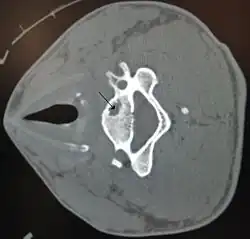

En radiographie, on peut repérer une géode par une image radiographique transparente :

- fond homogène ;

- contour tracé par une ligne continue ;

- cavité à contenu liquidien.